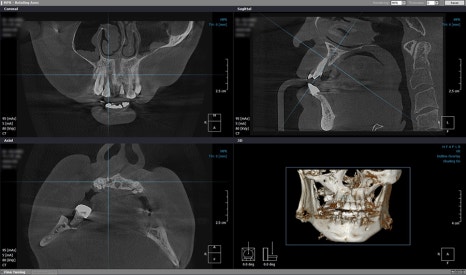

그 후 구내 상태 파악을 위해

3차원 정밀 투시 장비로

치조골, 신경, 혈관, 잇몸, 매복치 등을 촬영하고

구강 모식도를 디지털로 옮겨

적합한 잇몸뼈 자리를 선택한 뒤

시뮬레이션을 통해 오차 없는 설계를 이행합니다.